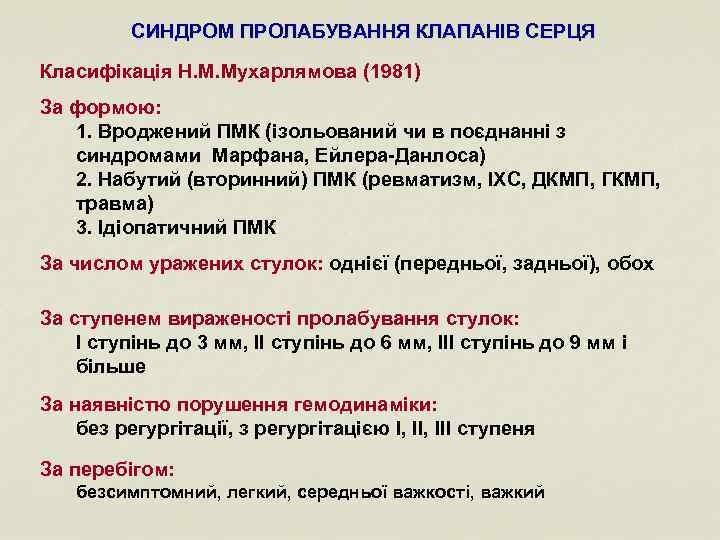

СИНДРОМ ПРОЛАБУВАННЯ КЛАПАНІВ СЕРЦЯ Класифікація Н. М. Мухарлямова (1981) За формою: 1. Вроджений ПМК (ізольований чи в поєднанні з синдромами Марфана, Ейлера-Данлоса) 2. Набутий (вторинний) ПМК (ревматизм, ІХС, ДКМП, ГКМП, травма) 3. Ідіопатичний ПМК За числом уражених стулок: однієї (передньої, задньої), обох За ступенем вираженості пролабування стулок: І ступінь до 3 мм, ІІ ступінь до 6 мм, ІІІ ступінь до 9 мм і більше За наявністю порушення гемодинаміки: без регургітації, з регургітацією І, ІІІ ступеня За перебігом: безсимптомний, легкий, середньої важкості, важкий